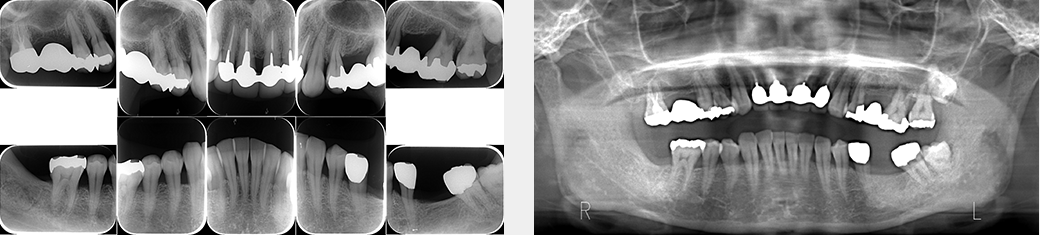

2.レントゲン検査

患歯だけでなく周辺の組織までを診断できるように数種類の撮影方法でデジタルレントゲン写真を撮影します。